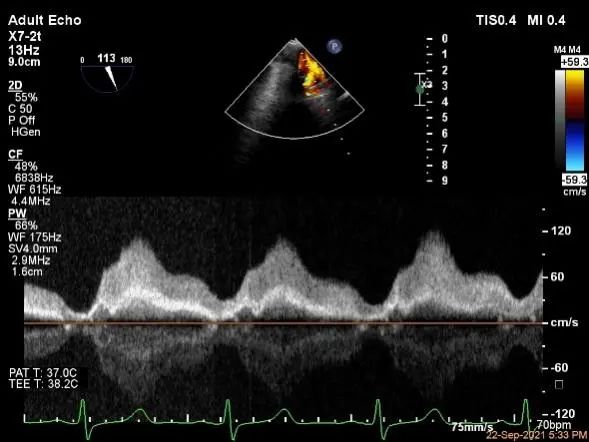

肺静脉血流频谱恢复正常